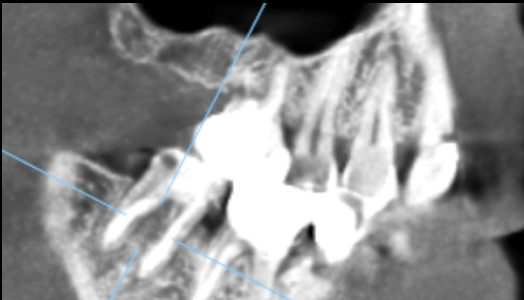

[60代男性]右奥歯から膿が出る[再生療法]

治療前

| 主訴 | 右奥歯から膿が出る 痛みが強い 歯を残したい |

| 治療内容 | 精密根管治療 歯周組織再生療法 セラミック修復 |